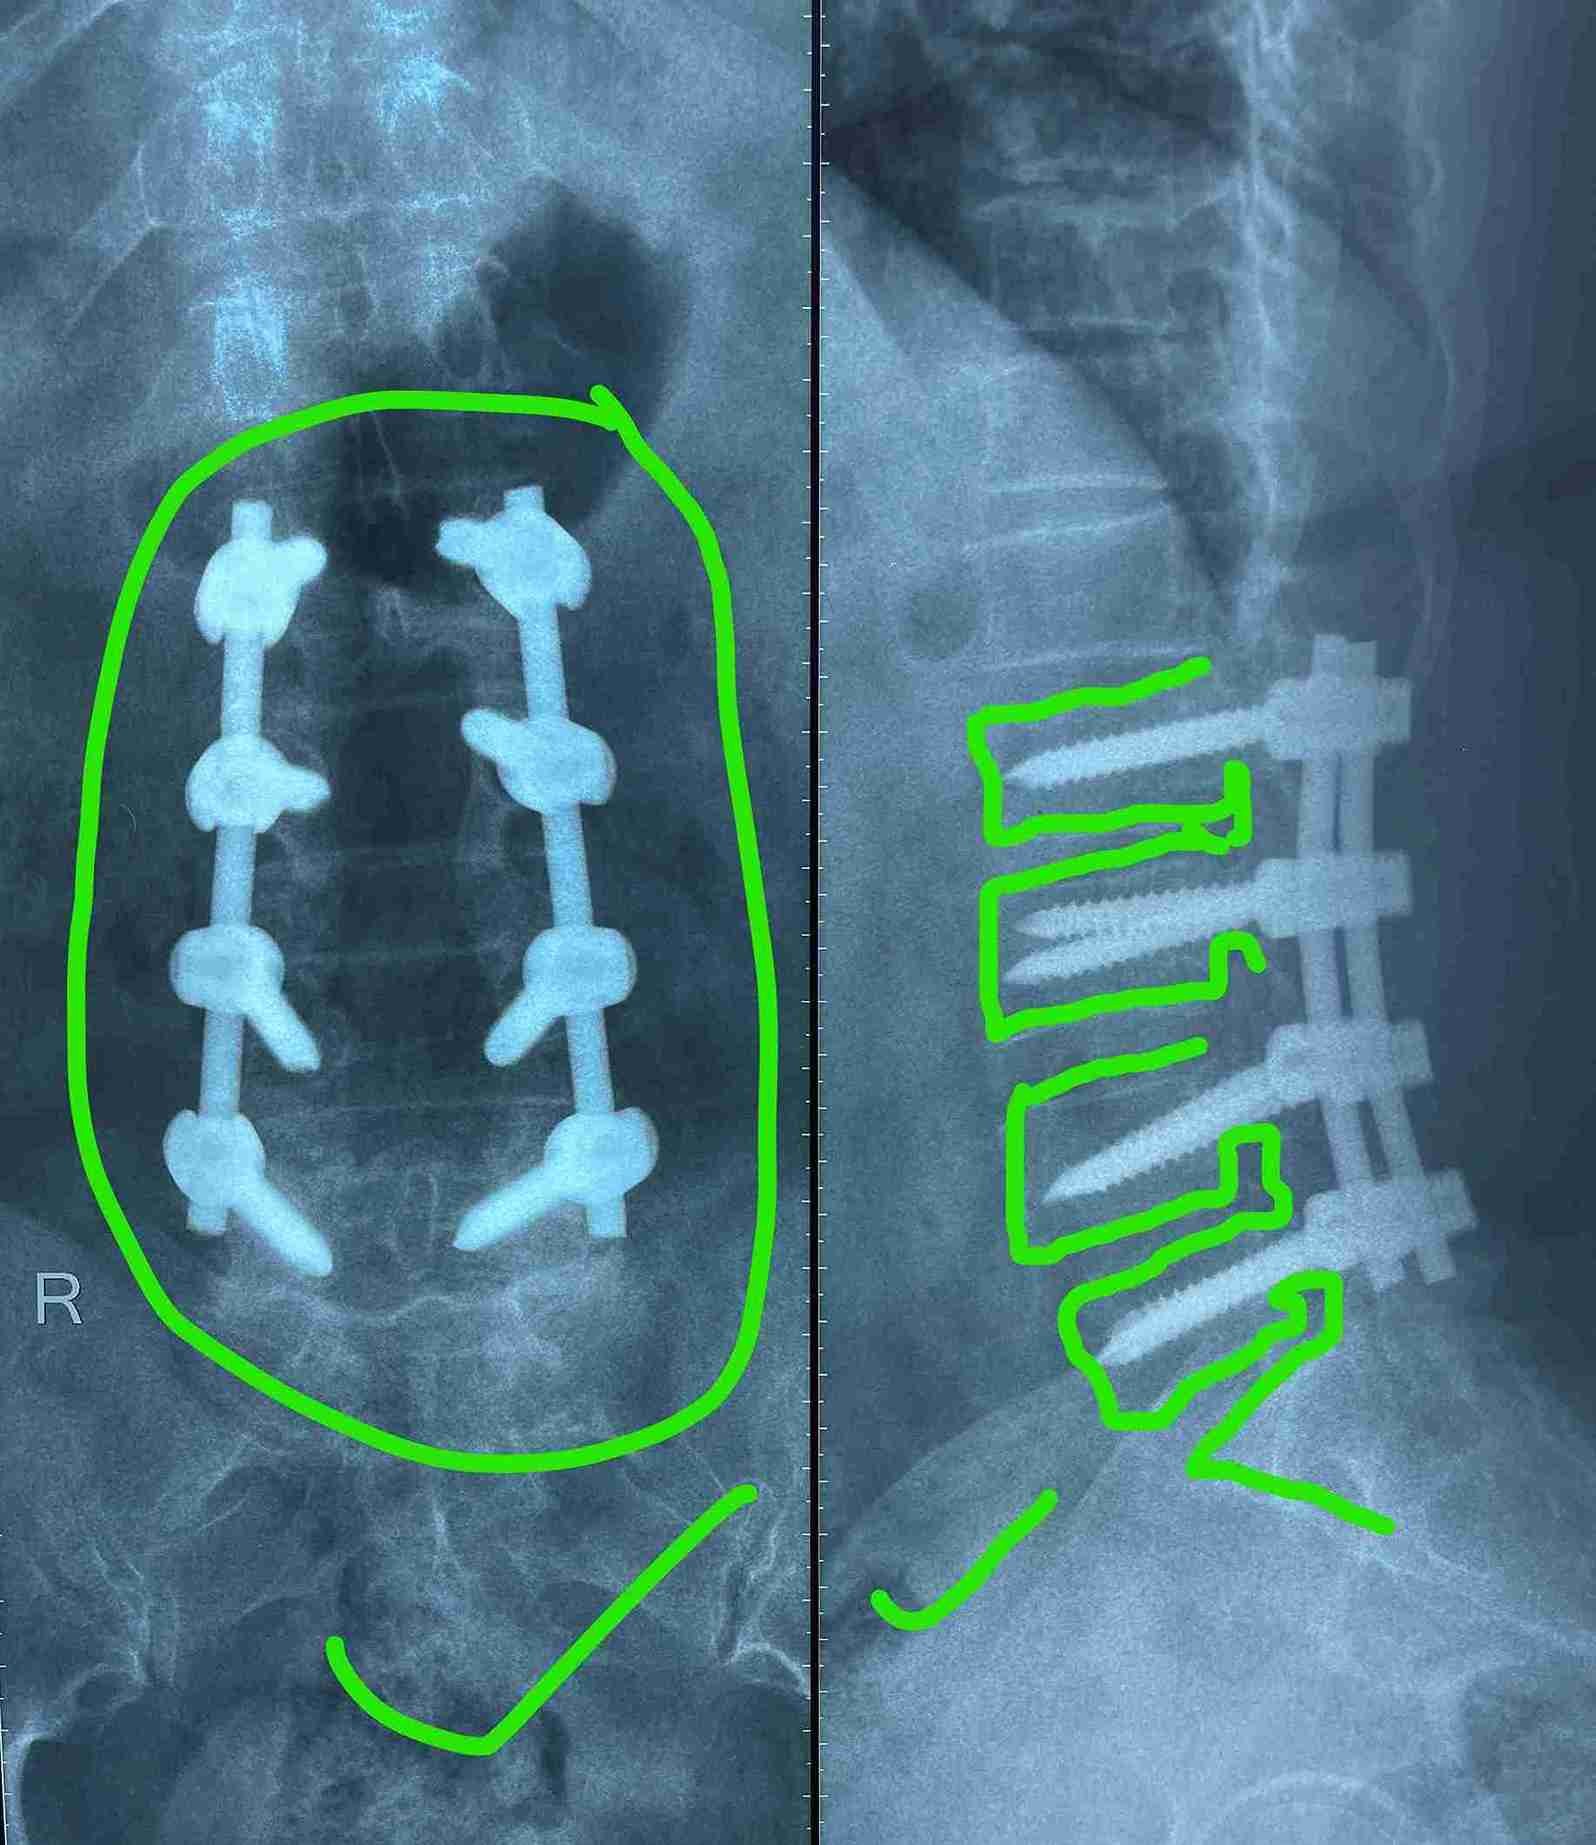

• Expanding the narrowed spinal canal at multiple levels

• Stabilizing the slipped vertebrae

• Relieving pressure on spinal nerves

• Restoring walking and movement ability

• Use of precision microsurgery techniques under magnification

• Advanced internal spinal fixation